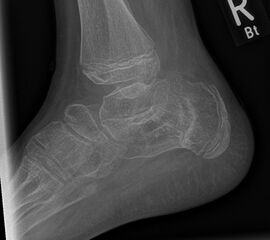

Welche minimalinvasiven fußchirurgischen Techniken in der Versorgung von Kinder- und Jugendfüßen geeignet und welche Indikationen sinnvoll sind, ist im Vergleich zu ausgewachsenen Füßen leicht abweichend. Hauptursache hierfür sind die Wachstumsfugen (Abb. 1).

Abb.1 a-b: Beispiel einer noch offenen Wachstumsfuge im dorsalen Bereich des Calcaneus: (a) Alter 6 und (b) Alter 9 Jahre.

Zum Lesen der Bildbeschreibung und zur Vollansicht bitte die Bilder anklicken. Bilder: A. Helmers.

In der Regel bestehen aktive Wachstumsfugen bei Mädchen bis zum 12. und bei Jungen bis zum 14. Lebensjahr, mit Abweichungen von einem Jahr nach unten und nach oben. Präzise Informationen unter anderem darüber gibt das präoperative Röntgenbild (Abb. 2).